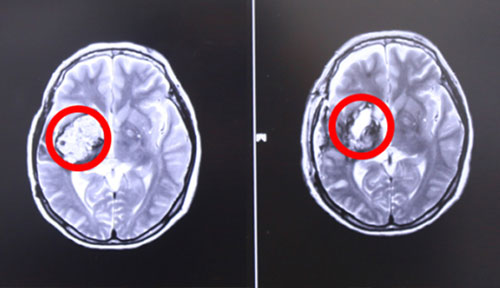

左側(cè)為術(shù)前,右側(cè)為術(shù)后,術(shù)后紅圈內(nèi)腫瘤物基本消失

17號上午9點左右,張XX被推入手術(shù)室,在全麻狀態(tài)下接受“右顳頂海綿狀血管瘤切除術(shù)”。至手術(shù)結(jié)束,已經(jīng)日暮時分。手術(shù)由經(jīng)驗豐富的侯增欣主任主刀,上顯微鏡,分離側(cè)裂,保護血管,切開顳上回皮質(zhì),見腫物呈暗褐色,靠近側(cè)裂動脈,并向大腦深部丘腦生長,術(shù)中顯微鏡下腫物近全切除,手術(shù)順利,腦神經(jīng)及血管保護完好,患者全麻醒,返ICU病房進行術(shù)后監(jiān)護。